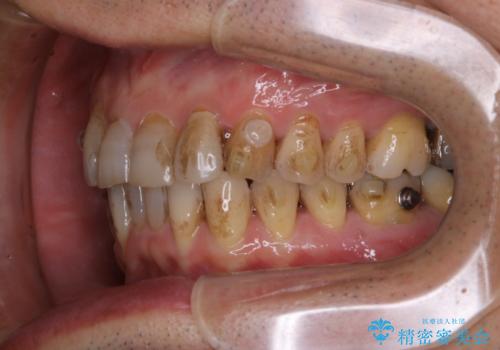

- インビザラインでの矯正中も、コーヒーを頻繁に飲むためステインが気になるとのことでした。PMTC60分コースでなんとかクリーニングを行いました。

インビザライン治療中には、歯の表面にアタッチメント(効率的に歯の移動をするもの)を設定します。そのため歯ブラシでは届きにくい細かい部分などに、歯石や着色がついてしまうことがあります。着色などを放置していると、着色なのか、虫歯なのかの判別もしずらく正確にお口の中の状態を診断できません。

※着色や歯石の量、お口の状態により60分コースでも全ての汚れを除去することができない場合もあります。